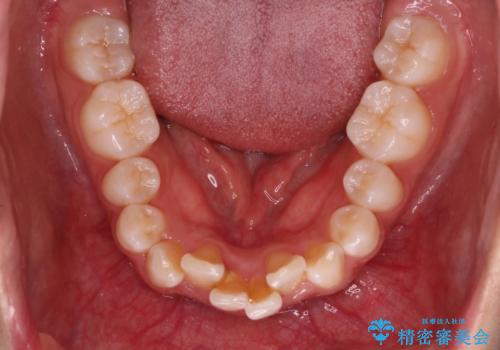

Invisalign インビザラインによる軽度なガタつきの改善

- 奥歯の位置関係はそこまで大きくいじらず、前歯群のみでガタつきの改善を計画しました

奥歯の位置関係に改善の余地はありますが、機能的に問題のない cusp to fossa の関係で咬めているため、前歯のガタつきを前歯のみで改善するというシンプルな計画で、短期間で治療を終了させました。